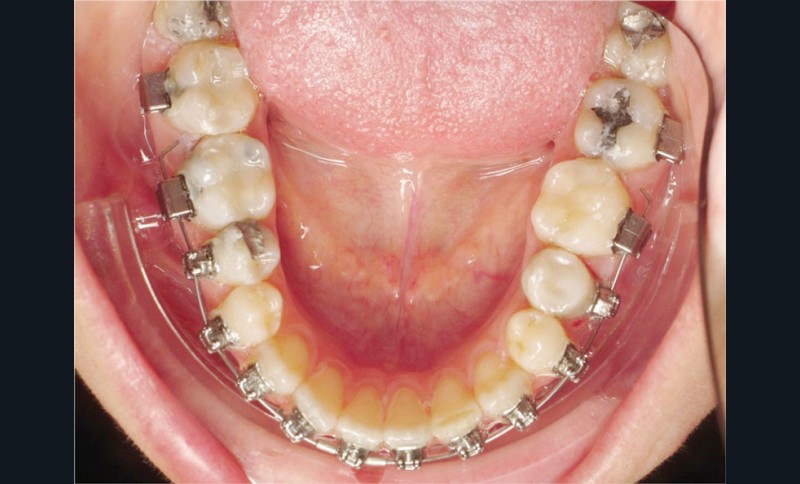

La patiente demande des attaches céramiques et nous trouvons un compromis en lui proposant un appareillage Insignia Damon Clear au maxillaire et Damon métallique à la mandibule.

Les empreintes ont été réalisées en sillcone wash technique et adressées au laboratoire Insignia. Actuellement, nous réalisons ces empreintes à l’aide de la caméra intra-orale Lythos et la fiche patient est initialement créée sur la caméra. Le transfert des empreintes au laboratoire est immédiat et le risque d’erreurs considérablement réduit (fig. 4 à 6).